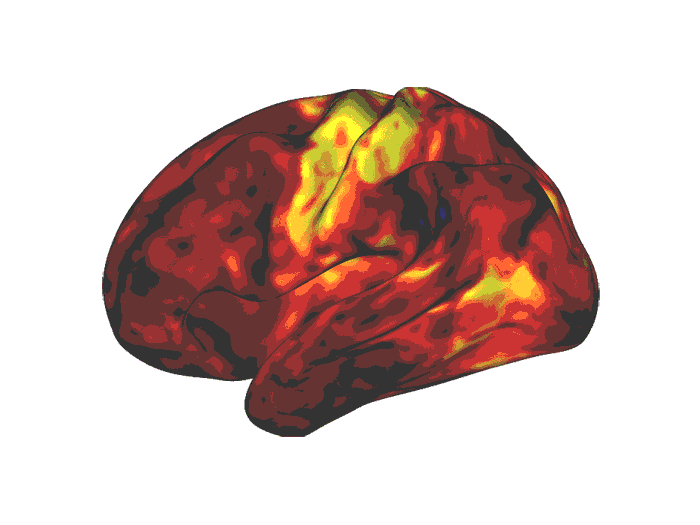

What the team saw in both the children and adults were changes in brain connectivity in the wakefulness and reward centers of the brain, activated by the medication – not, as might have been expected, the attention centers.

Brain areas highlighted in yellow and orange were activated by the stimulant drugs. These are regions associated with wakefulness and reward.

Image credit: Benjamin Kay